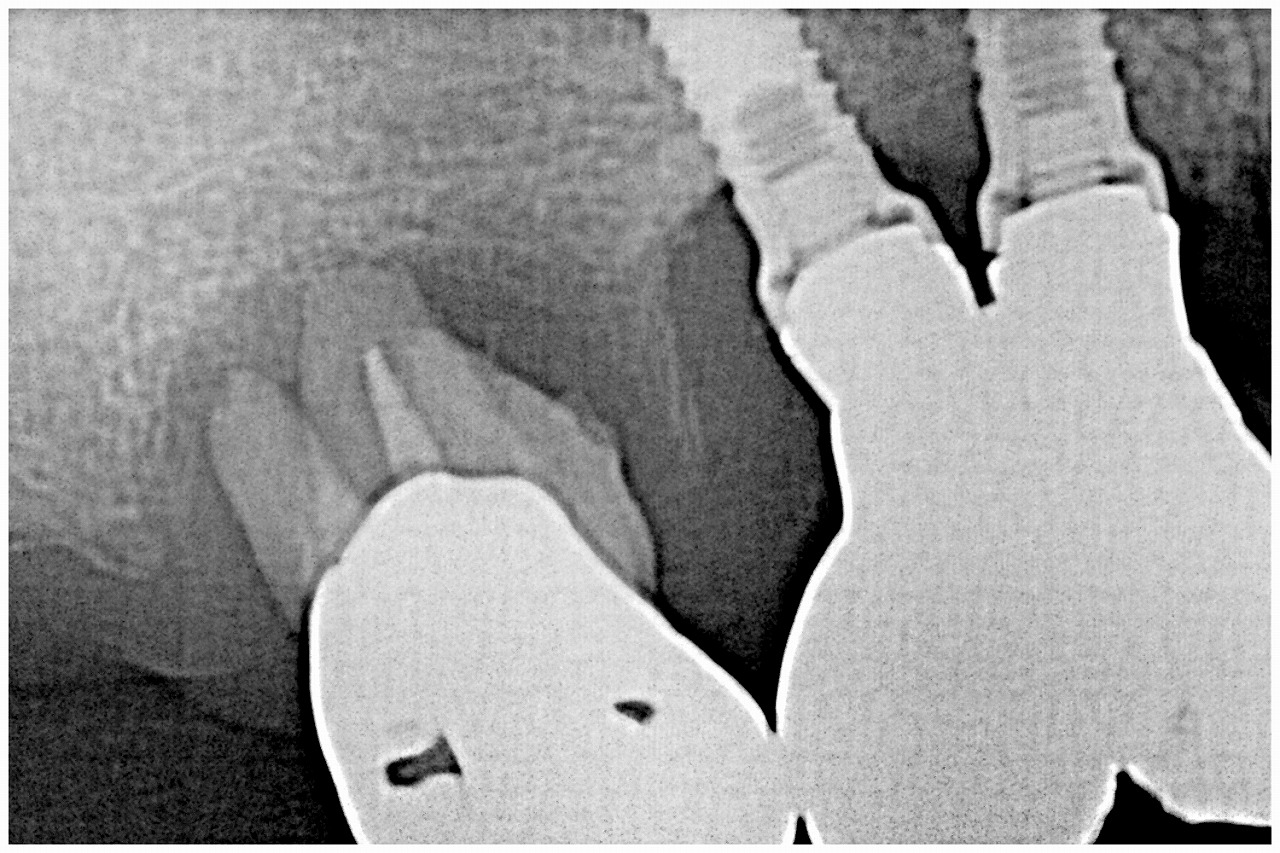

6番が根尖まで骨吸収が進み抜歯の歯となっていました

アバットメントを取り出してみていきます

インプラント感が近接しており補綴も頬側方向に向いており、

難しい補綴がしてありました